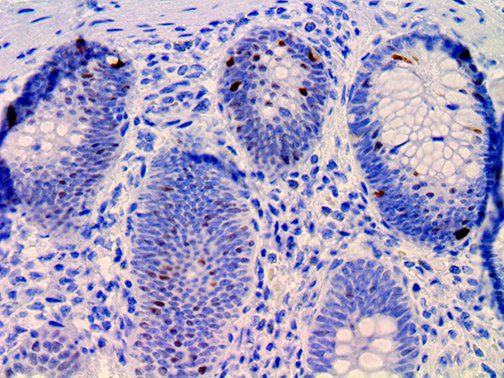

The first cytokines released are interleukin 1β (IL-1β) and tumor necrosis factor-α (TNF-α), which attract a variety of circulating white blood cells (WBCs) to the infection site, including neutrophils, monocytes, macrophages, and natural killer (NK) cells. This response, along with the antipathogenic chemicals released by these cells (i.e., complement), comprise the innate immune response. These cells directly attack the invading pathogen and also release additional cytokines, chief among them interleukin-1 and 6 (IL-6). IL-6 is essential for invoking the adaptive immune response, which calls T-cells, B-cells, and T helper (Th) cells to the infection site. IL-6 also stimulates further recruitment, proliferation and activation of macrophages.

This activation induces inflammatory monocytes to highly express IL-6, starting a localized and then systemic cascade effect that results in hyperproduction of IL-6, which accelerates the inflammatory process. Because IL-6 also increases vascular permeability, excessive levels cause blood vessels to become very leaky. This, along with clotting factors released from vascular endothelial cells, stimulates the coagulation cascade, resulting in microthrombosis (tiny clots), which leads to ischemia and tissue death of the kidney, intestines, heart, liver, brain and extremities.